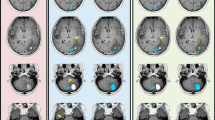

Decay curves of T2 and T2* for a healthy volunteer using: the three shim techniques (A, B), pixel sizes of 2 × 2 to 4 × 4 mm for T2 (C), pixel sizes of 1 × 1 to 3.28 × 3.28 mm for T2* (D), slice thicknesses of 8, 10, 12 mm (E, F), TR values 245–500 ms for T2 (G) and TR values 100–230 ms for T2* (H).

Figure 5A,B present typical images of a patient acquired using standard and optimised T2*, while Fig. 5C,D obtained using standard and optimised T2, respectively.

In general, there was a slight difference in magnitude measurements between the conventional and optimised T2 sequences for patients studies (Figs. 3, 4). The conventional sequence provided a higher measurement by 1.5% and higher SD by 4% than its corresponding optimised sequence. The correlation coefficients obtained from the conventional sequence were 0.978–0.994, whilst for the optimised sequence the range was 0.979–0.994 (p < 0.01). We also observed similar image qualities were obtained for the patients using the T2 and T2* optimised sequences as compared to their corresponding standard sequences (Fig. 5).